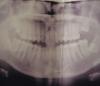

applem Опубликовано 28 апреля, 2011 Автор Поделиться Опубликовано 28 апреля, 2011 Добавляю фотографию ортопантомограммы до удаления 7 справа вверху. После удаления есть КТ, но не знаю как его сюда выложить... Ссылка на комментарий

applem Опубликовано 27 апреля, 2011 Поделиться Опубликовано 27 апреля, 2011 Ситуация такая: сверху удалена семерка. Восьмерка ретенирована, стоит ровно, но далеко от шестерки. Одни врачи советуют удалить восьмерку и поставить имплант на место 7, а другие говорят ни в коем случае не удалять, пусть 8 попробует вылезти. С нижними тоже мнения разошлись: все нижние есть, но обе 8-ки ретенированы, уперлись под углом в 7ки. Периодически ощущаю сдавливание передних зубов. Одни врачи посоветовали удалить обе нижние 8ки, другие говорят, что это очень сложно и опасно, лучше не трогать - ничего с передними зубами не случится.Что делать, кому верить не знаю. Иногда кажется, что некоторые стоматологии готовы и больные и здоровые зубы поменять на импланты, лишь бы денег побольше заработать. Ссылка на комментарий

Штаматолог Опубликовано 28 апреля, 2011 Поделиться Опубликовано 28 апреля, 2011 Верхние 8-ки попробовать вытянуть ортодонтически на место 7-ок. Нижние - удалить. Ссылка на комментарий

Штаматолог Опубликовано 29 апреля, 2011 Поделиться Опубликовано 29 апреля, 2011 А сами 8-ки не вылезут?Судя по тому, что корни уже полностью сформированы - нет. Вам лет сколько? Ссылка на комментарий